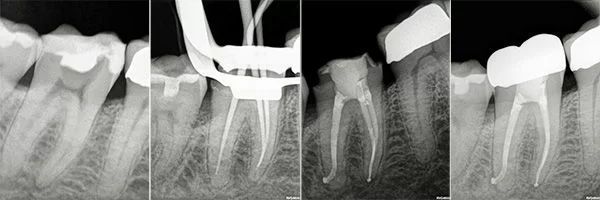

Root Canal in Morocco Before and Afters

Certified Endodontists with Microscope and Laser.

Check out our Before and Afters

Root Canals are done by an Endodontist and require the Specialist to make a hole through the enamel and dentin surfaces to gain access to the pulp chamber, where the Endodontist proceeds to remove the pulp, clean the pulp chamber and seal the chamber with gutta-percha. To ensure the long-term success of the tooth after a Root Canal an antibiotic is prescribed and a Post and Core Build-Up and Crown are recommended to prevent fractures or filtration of bacteria to the tooth.

Step-by-Step Root Canal Procedure

- At the beginning of the procedure, the dentist will isolate the tooth using a rubber dam and anesthetize the tooth sufficiently to prevent pain while performing the procedure.

- The dentist uses a drill to access the pulp chamber and related canals of the tooth. This allows inserting specialized dental instruments to clean the pulp chamber and root canals. Then the specialist cleans completely the remaining space and shapes it to make space for a filling. The filling will replace the pulp in the tooth.

- The dentist fills the Root Canal with a bio-compatible material. Gutta-percha and Adhesive dental cement are good options to seal the root canal. Sealing prevents future infections in the area.

- A temporary filling is placed in the hole used to access the root canals. Once the dentist deems the tooth is healing properly and the root canal is a success, he places a permanent restoration.